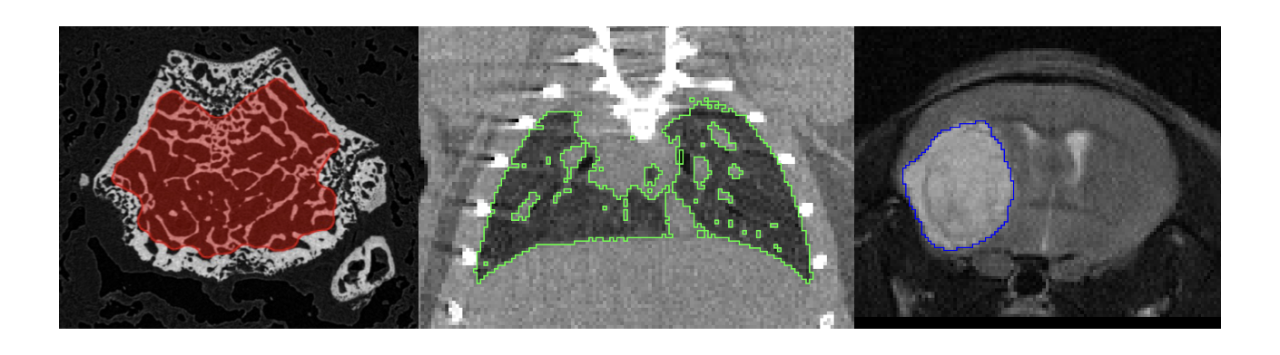

• Multimodality segmentation tools – comprehensive semi-automated and manual tools for precision and reproducibility

• Full access to metadata – ensure accurate calculation of Standard Uptake Value and other key statistics

• Flexible switching between 3D and 4D datasets – direct output of time activity curves